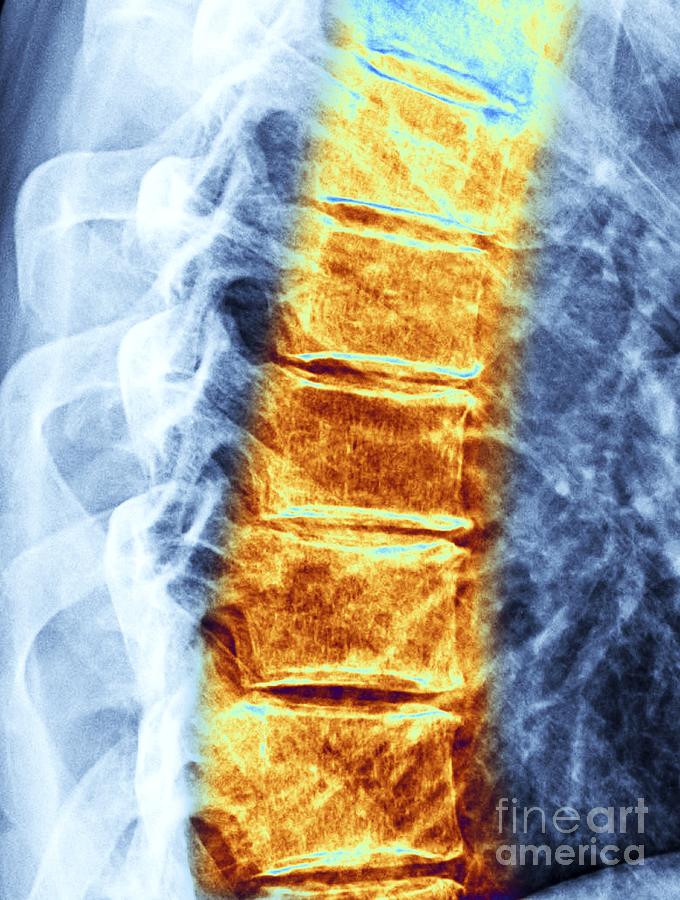

From pixels.com

Arthritis Of The Spine Photograph by Zephyr/science Photo Library Pixels Arthritis Symptoms Spine Thoracic Osteoarthritis pain in the thoracic region of the spine is usually provoked by movement of forward flexion and hyperextension. Symptoms of spinal arthritis may differ from person to person. What are the symptoms of spinal arthritis? Back pain (especially neck pain and lower back pain). What are spinal arthritis symptoms? The most common spinal arthritis symptoms include: Other symptoms of. Arthritis Symptoms Spine Thoracic.